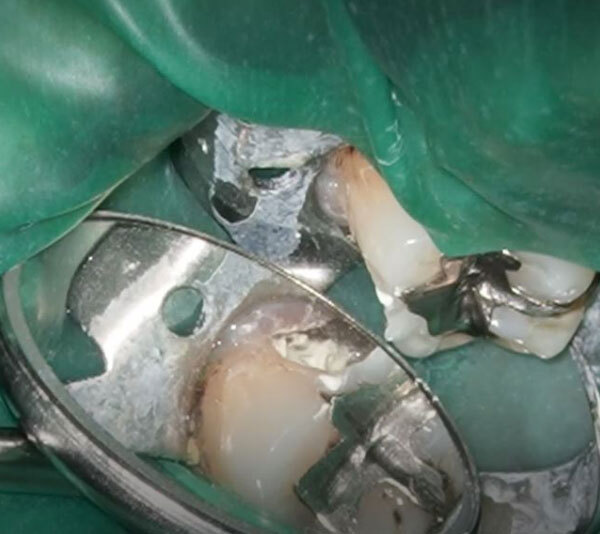

残っている虫歯を慎重に取っている所です。

マイクロスコープを使用することで、虫歯の部分のみを選択的に取り除くことが出来ます。また、神経が露出した際にお口の中の細菌に曝されないようにするために、ラバーダム防湿を行ってやっております。

虫歯を全て取り切っても神経は露出しませんでした。

しかし、神経との距離は薄皮一枚程度で象牙質の構造を考えると、材料による裏打ちを行った方が神経への刺激を防げられるので、今回はMTAにて裏打ちをしていきます。その上から仮の材料を詰めて削った部分を暫間的に封鎖していきます。